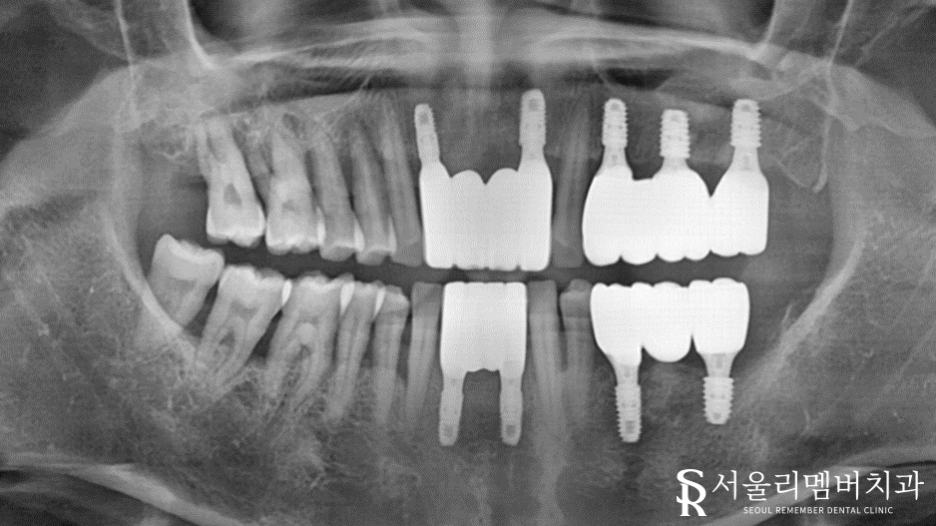

픽스처 위에 올리는 최종 보철은 눈에 잘 띄는 곳에 있기 때문에

아무래도 심미적인 면을 중요시할 수밖에 없죠.

이때 심미적이라 하면 하얗고 올바른 형태만 떠오르실 텐데요.

그렇지만 환자께서 본래 갖고 있던 자연치와 유사하게 제작하는 것이 더 좋은 보철이라 할 수 있습니다.

따라서 치경부 라인 및 치아 형태 분석을 통해 최종 보철 제작을 마쳤습니다.

한눈에 봐도 어떤 게 보철인지 구분이 잘 가지 않는데요.

만약 이분께 사용했던 보철을 다른 분께 올려드리면 절~대 어울리지 않을 겁니다.

즉, 개인의 분위기, 안모, 입매, 성별 등을 분석하여 1:1 맞춤 제작을 진행해야 되죠.

환자께서도 통증은 물론이며 티가 나지 않는 외관도 마음에 쏙! 드신다는 말씀을 남기셨습니다ㅎㅎ